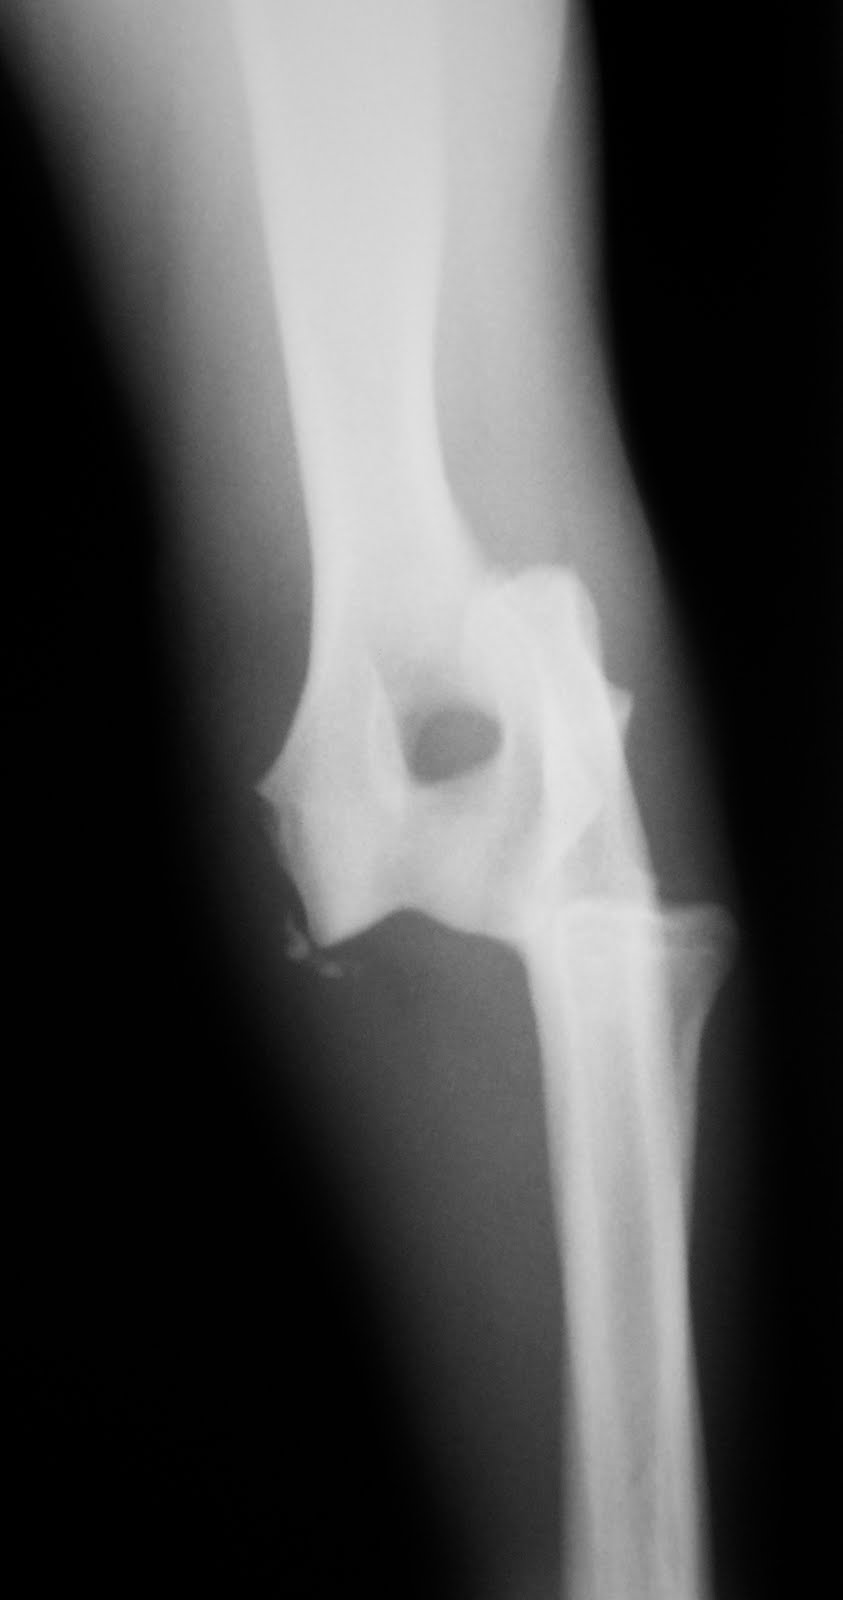

Βρέθηκα στο άλσος Συγγρού με τραυματισμένο το πρόσθιο δεξιό άκρο μου. Προσκομίστηκα στο Κτηνιατρικό Κέντρο Ιλισίων όπου διαπιστώθηκε ότι είχε εξαρθρωθεί ο δεξιός αγκώνας μου. Το εξάρθρημα ανατάχθηκε και τοποθετήθηκε νάρθηκας.